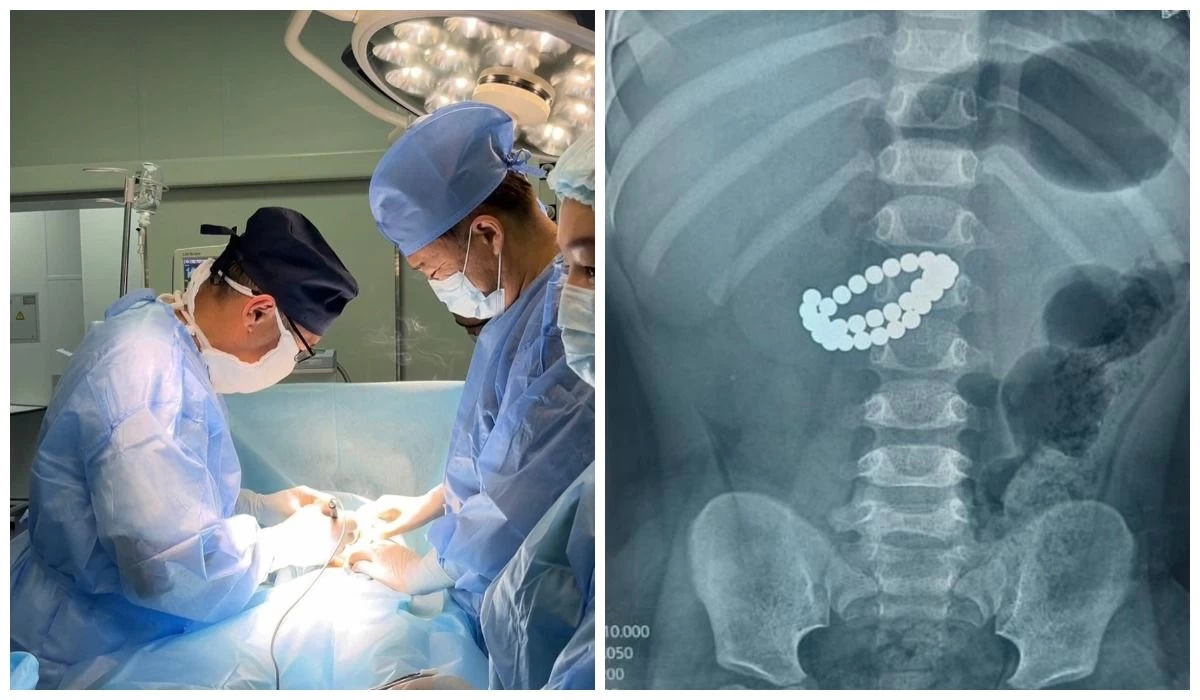

Алматыда дәрігерлер 1 жасар баланың ішінен 31 магнит алып шықты

Алматы әкімдігінің мәліметінше, бала 31 магнит жұтып қойып, ішегіне ауыр зақым келіп, перитонит белгілерімен өте ауыр жағдайда жеткізілген.

Хирургтер магниттерді алып, жіңішке ішектегі зақымдарды қалпына келтіріп, құрсақ қуысын толық тазарту шараларын жүргізген. Дәрігерлердің айтуынша, бұл ота баланың өмірін сақтап қалудың жалғыз жолы болған.

Фото: Алматы әкімдігі

“Мамандар тіпті бір ғана магниттің өзі қауіпті екенін айтады. Бірнеше магнит ағза ішінде өзара тартылып, ішкі тіндерді зақымдап, санаулы сағаттың ішінде ауыр асқынуға әкелуі мүмкін”, – делінген әкімдік хабарламасында.